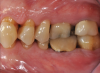

Fig 3. Pretreatment views: right lateral (Fig 2), frontal (Fig 3), and left lateral (Fig 4). Note: The maxillary right first molar (tooth No. 3) (Fig 2) would be identified as the most periodontally involved molar that was planned to be maintained.

Figure 3

Periodontal examination revealed generalized BOP and PDs up to 9 mm in the maxillary and mandibular molars with multiple furcations in each molar (Figure 2 through Figure 7). He presented with class I mobility in many posterior teeth and class II mobility in teeth Nos. 3 and 9 (maxillary right first molar and maxillary left central incisor, respectively). The periodontist decided to score tooth No. 3 for the PRS, as this was the most periodontally involved molar that was planned to be treated and maintained (Figure 2 and Figure 8). This tooth (maxillary right first molar = score 1) presented with probing depths of 7 mm (score 1); three total furcation invasions (score 3) (mesial [degree II furcation], buccal [degree I furcation], and distal [degree II furcation]); and a class II mobility (score 2). The total PRS for tooth No. 3 was 8, representing a "guarded" prognosis. Based on this score, the likelihood of not losing any teeth to periodontal disease for 15 years was 81%, and for 30 years the likelihood was just 56% (Figure 9).7